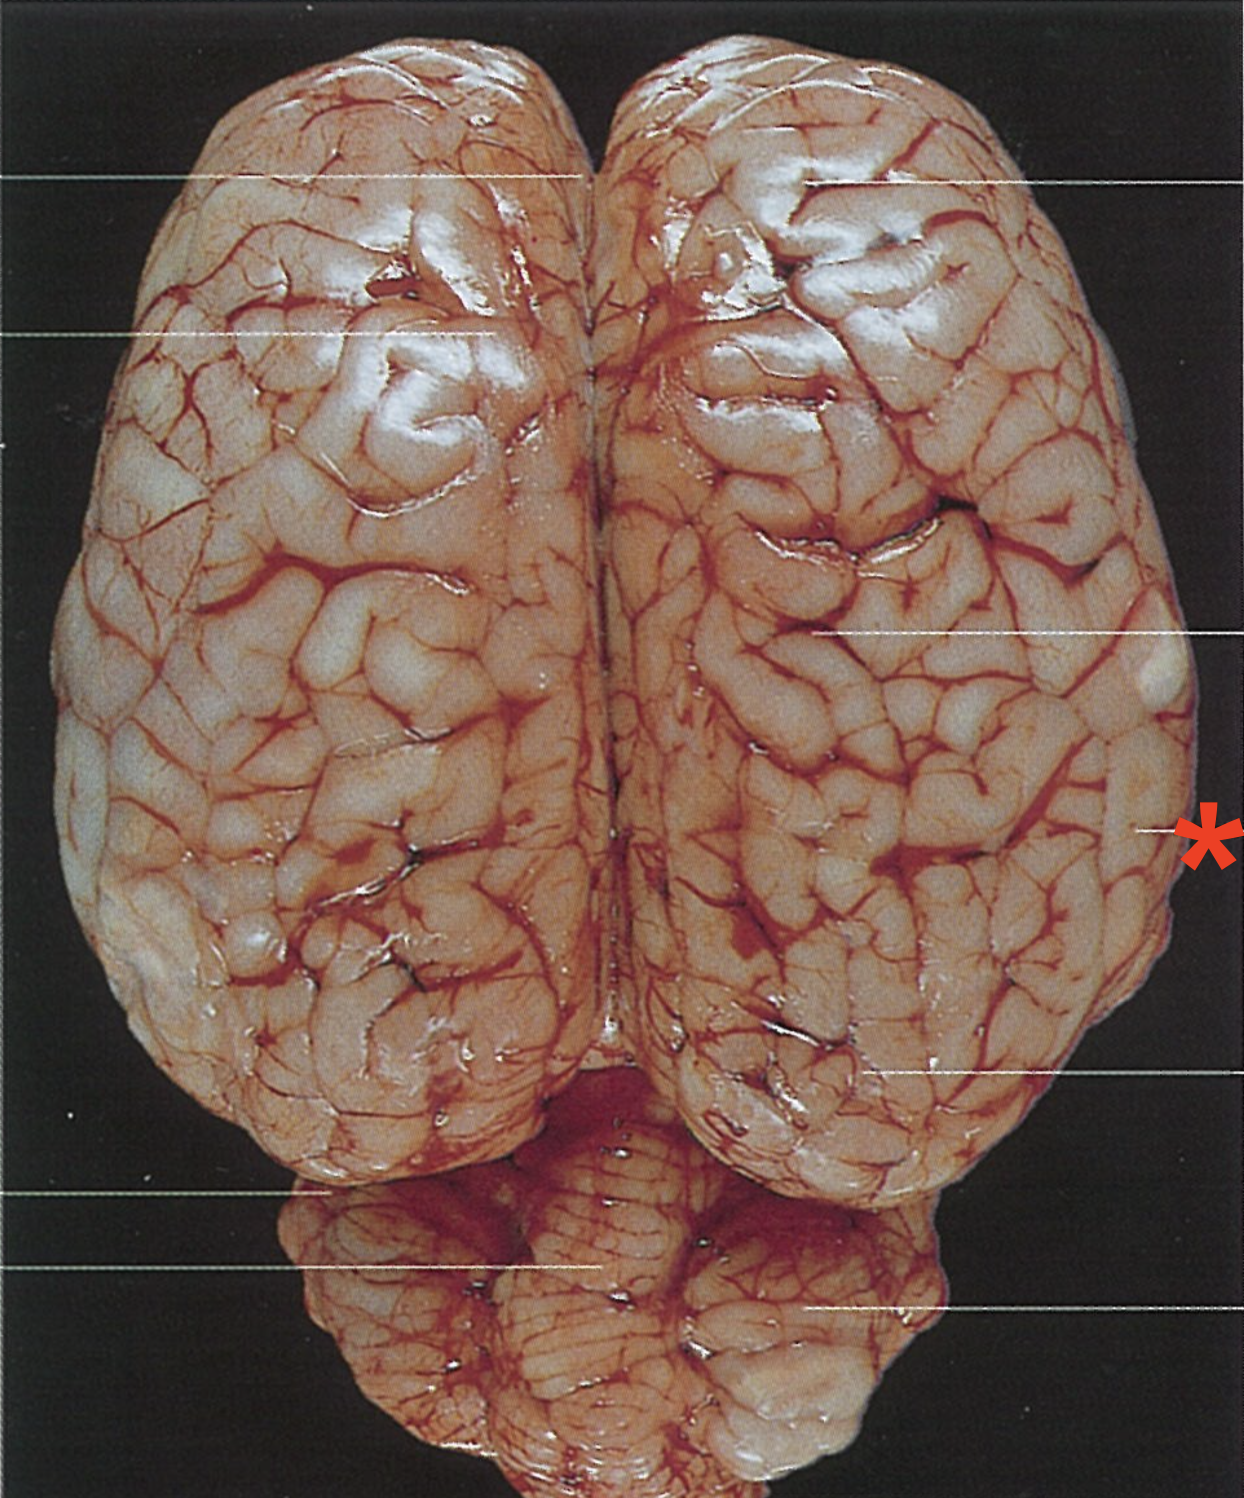

What is the telencephalon composed of?

Paired cerebral hemispheres

Longitudinal cerebral fissure

Frontal lobe

Parietal lobe

Temporal lobe

Occipital lobe

What are the elevated bands found on the surface of the telencephalon hemispheres?

Gyri cerebri

What separates the gyri cerebri?

Sulci cerebri

Transverse fissure of the cerebrum

3

Fissura sylvia (Un.)

5

Sulcus diagonalis (Un.)

7

Sulcus presylvius

4

Fissura ectosylvius rostralis